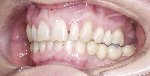

Eine absolute ästhetische Integration des künstlichen Zahnes kann nur dann erzielt werden, wenn die im Mund eingegliederte künstliche Krone nicht als solche zu erkennen ist.

Sowohl natürliche als auch künstliche Zähne sind Elemente eines Gesamtbildes, die noch durch die parodontalen Strukturen (rote Ästhetik) und die umgebenden Elemente (Lippe, Wange, Gesichtsmuskulatur) enthalten.

In diesem Zusammenhang ist für ein ästhetisches Ergebnis nicht nur die richtige Planung und Durchführung der Therapie seitens des Behandlers wichtig, sondern auch die kreative Umsetzung des Zahntechnikers unter Berücksichtigung des umgebenden Weichgewebes (Emergenzprofil) und des Gesichtes, um den Patienten durch die neue Krone Schönheit und Harmonie zu verleihen.